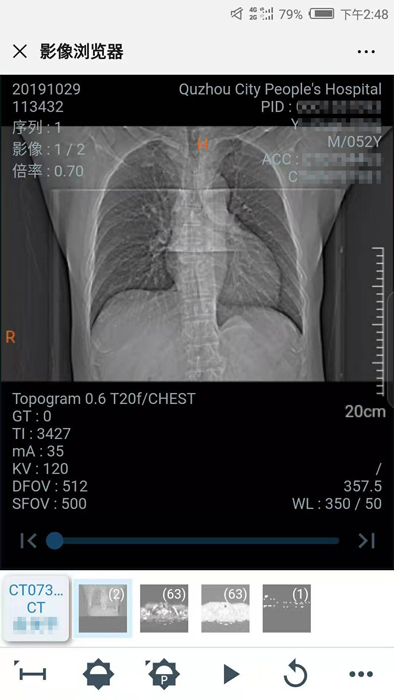

10月29日晚,我院向住院患者推行數(shù)字影像服務(wù),云膠片正式上線!點點手機就能查看片子不限次數(shù)瀏覽影像……方便、省錢、精準(zhǔn)、環(huán)保,“云影像”服務(wù)平臺讓您看病更省心。

10月30日,住院患者俞先生收到一條短信提醒“【云影像】衢州市人民醫(yī)院提醒您,俞先生的CT報告已完成……”俞先生隨即點擊手機上的瀏覽鏈接,輸入身份證后六位,驗證完成,短短幾秒鐘,躺在病床上也能查看到自己的CT電子報告和影像,俞先生直呼神奇。

“醫(yī)院面向住院患者全面推行檢查檢驗結(jié)果電子化,互認共享,全面提供網(wǎng)上查詢、移動推送等服務(wù),‘云影像’平臺的運行就是深化‘最多跑一次’改革要求的又一新舉措?!贬t(yī)院信息處工作人員介紹,“ ‘云影像’是儲存在云端的病人醫(yī)學(xué)影像檢查信息,包括檢查報告、電子膠片及供專業(yè)影像科醫(yī)生診斷瀏覽的全部醫(yī)學(xué)數(shù)字原始影像。放射檢查報告完成后,醫(yī)院會同步發(fā)送提醒短信到患者的手機上,只要點擊短信上的鏈接就可第一時間獲取‘云影像’及報告。使用‘云影像’查看檢查報告,解決了排隊取片、復(fù)診帶片的煩惱,縮短了就醫(yī)時間,讓老百姓看病得到實實在在的方便?!?